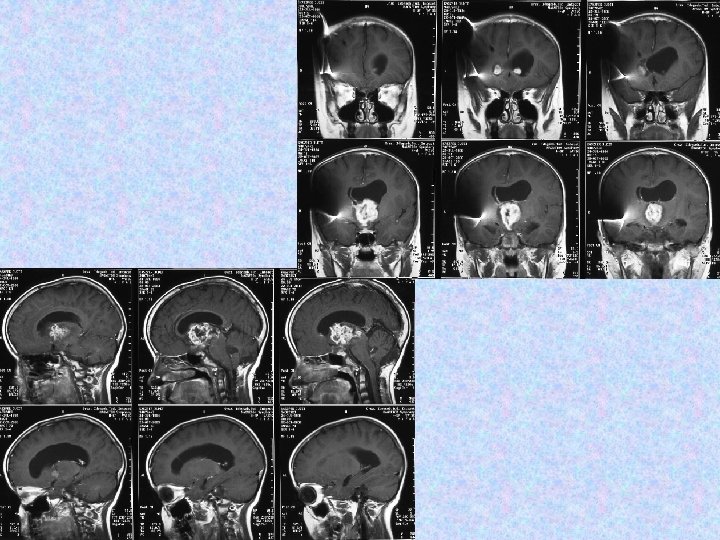

• A 2006. szeptember 27 -i MRI összevetve a 2005. november 16 -i MRI-vel: a halmozás amorf formájú növekvő tumor masszát mutat mindkét frontális kamraszarvban. A kamrarendszer továbbra is tág. A caudalis durazsák halmozó tumor masszával kitöltött.

• A következő műtét 2006. októberében történt. Részleges eltávolítás, aqueductoplasica történt. Szövettan pilocitás asztrocitómát igazolt. • 2006. 12. 16 -án készült MR vizsgálat kiterjedt intraventriculáris, subarachnoideális, thoracolumbális halmozási többletekkel járó teljes neuraxist érintő disszeminációt ábrázolt.